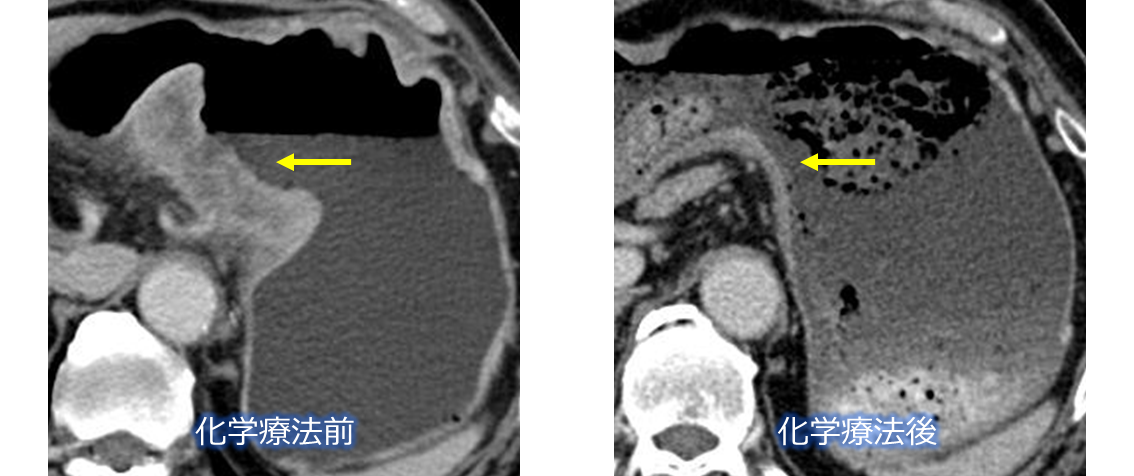

化学療法で消失した大型胃がん

化学療法で消失した高度リンパ節転移胃がん